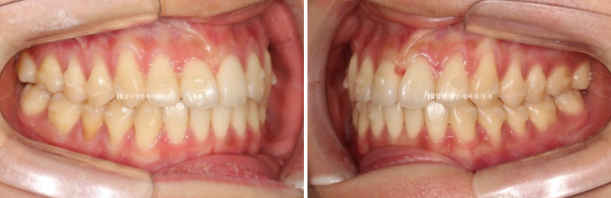

치료 전 - 치료 후 비교 사진입니다.

초진 24.02 이며 치료 종료는 24.07입니다.

24.02~24.07

소량의 치간삭제로 블랙트라이앵글 없이 치료를 마무리 했습니다.

좋은 교합은 유지가 되었고

토끼이빨은 정상 배열을 찾앗습니다.